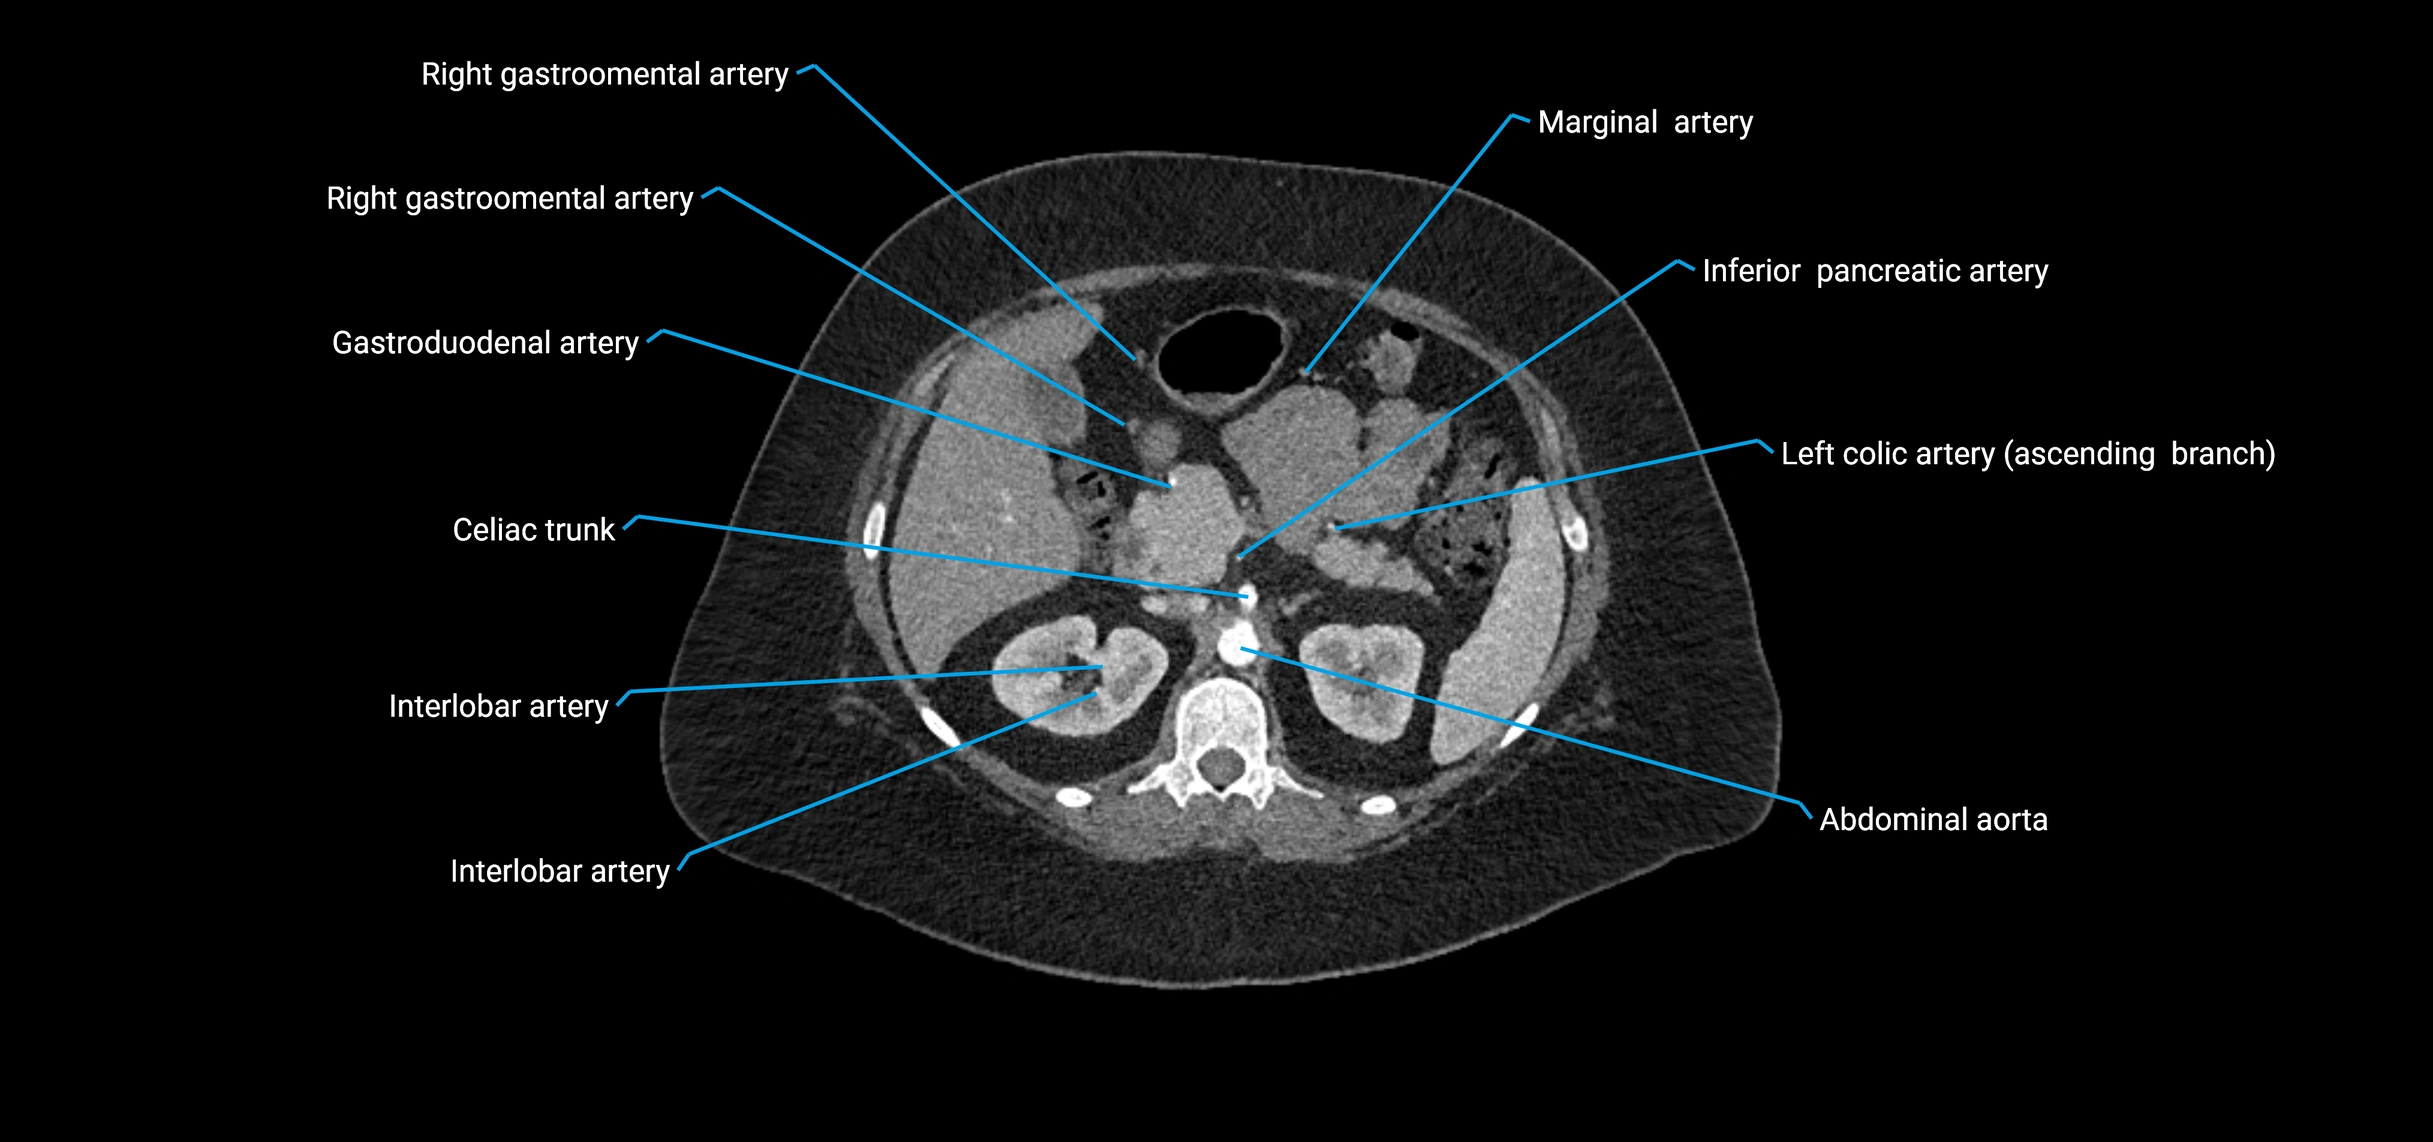

CT Appearance

Non-contrast CT:

• Appears as a tubular soft tissue structure anterior to vertebral bodies

• Calcified atherosclerotic plaques appear as hyperdense foci along the wall

• Useful for screening abdominal aortic aneurysm (AAA) size and mural calcification

Contrast-enhanced CT (CTA):

• Gold standard for abdominal aortic imaging

• Provides excellent detail of lumen, wall, aneurysm, thrombus, and branch vessels

• Multiplanar and 3D reconstructions help in aneurysm measurement, stent graft planning, and dissection evaluation

• Detects acute rupture, traumatic injury, or occlusion with high sensitivity

CT images

image